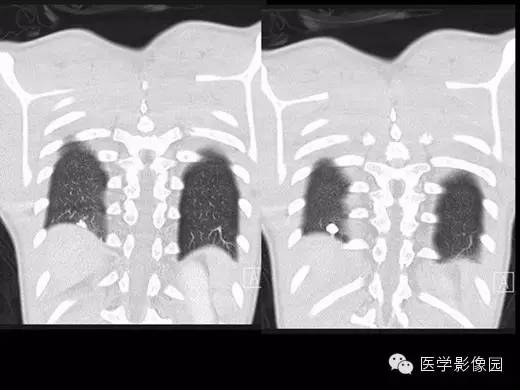

X线检查、CT:可见肺、肝、脾等脏器可有许多钙化点。纵隔组织胞浆菌病还包括纵隔的肉芽肿和纤维化性纵隔炎。组织胞浆菌病大多数不需要特殊治疗,通常经过卧床休息、加强营养等支持疗法后,多在3个月至数年间自然痊愈。